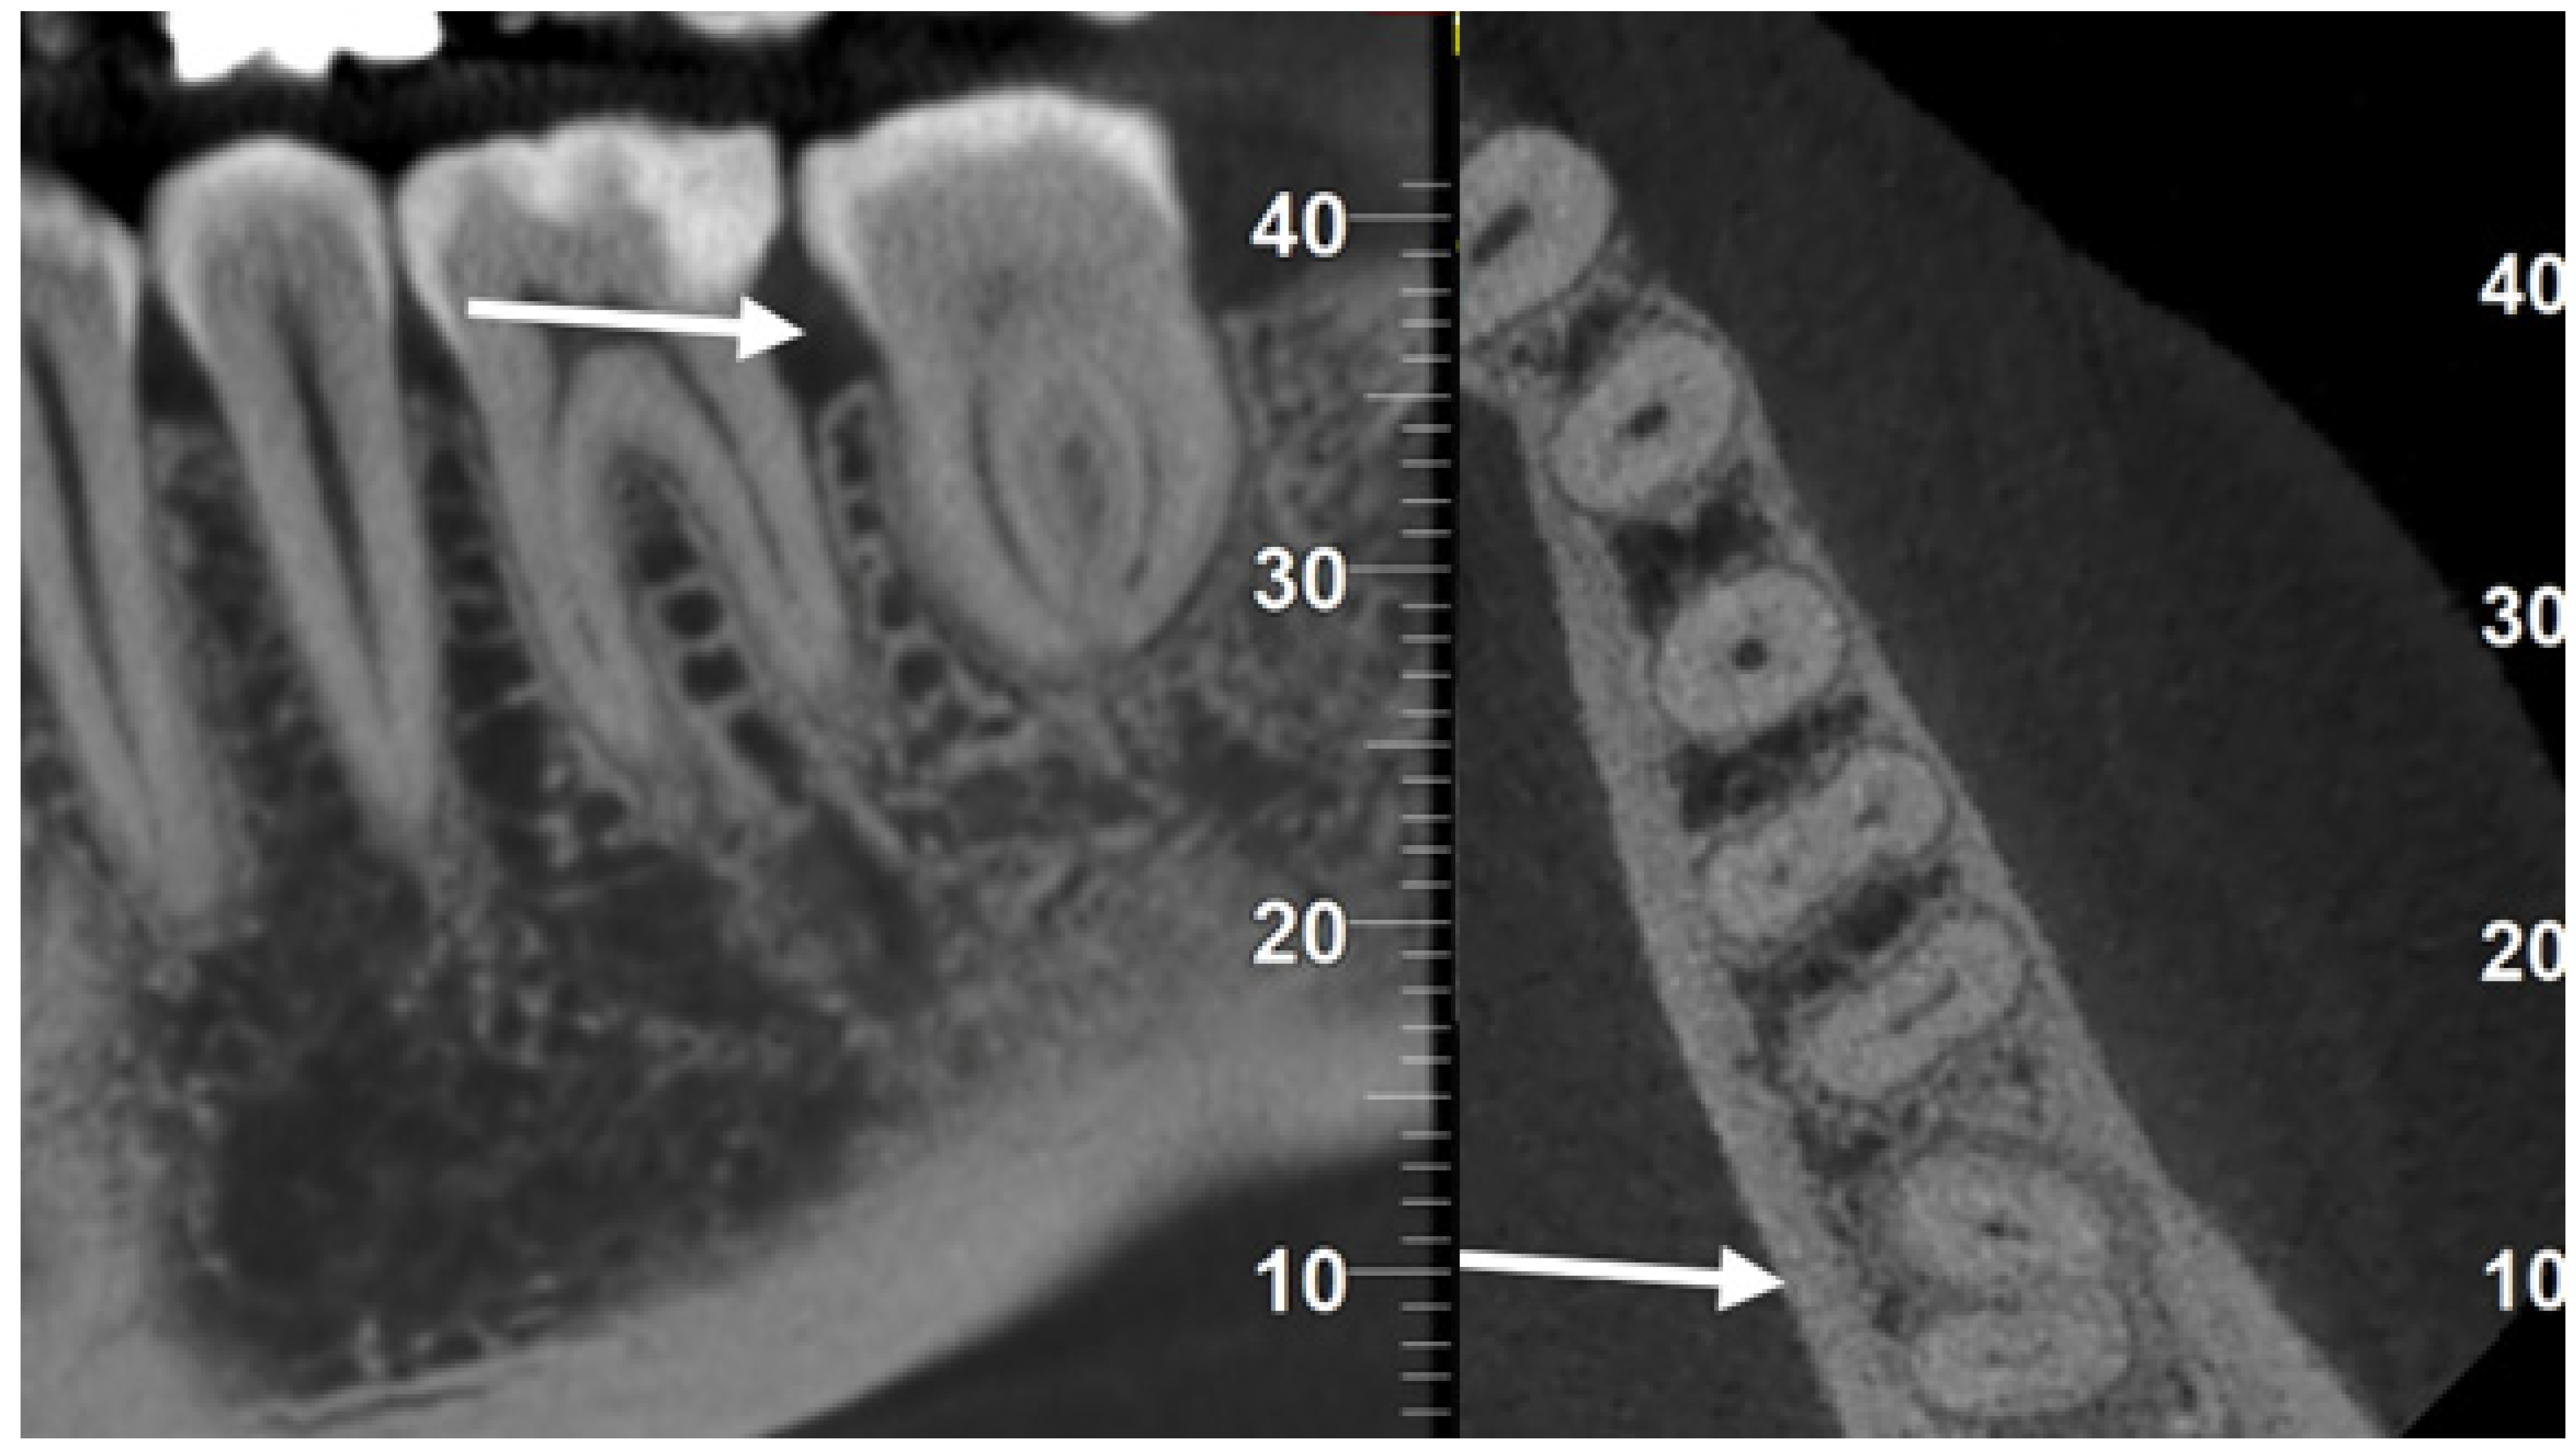

After five years, the patient underwent a CBCT for other reasons. It was possible to exclude the presence of peri-radicular lesions or resorptions, confirming complete healing without complications, even without root canal treatment in a mature tooth (Figure 4).

In the present case, at the five-year follow-up visit, the transplanted tooth did not show any sign of periapical reaction or resorption, demonstrating the reliability of the atraumatic extraction and preparation of the recipient socket. Moreover, no root canal treatment was necessary, probably due to the maintenance of the asepsis of the endodontic spaces during the transplantation. We do not know if pulp tissue is still vital or if it underwent aseptic necrosis and has been replaced by PDL-like tissue, as occurs in pulp revitalization [20]. Still, the goal, in this case, was to obtain healing in a mature donor tooth without endodontic treatment.

Figure 4. CBCT images at five years showed complete healing even though the transplanted donor tooth (arrows) was not endodontically treated.